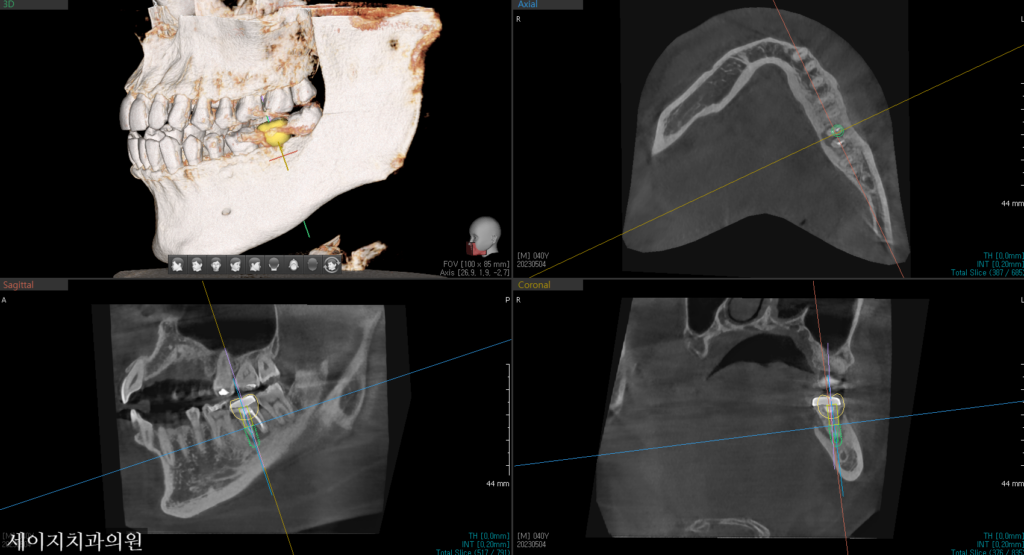

사진 설명을 입력하세요. 해당치아는 광범위한 골소실로 인해 발치로 치료계획을 설정하였습니다. 3D CT 장비를 이용하여 해당 부위의 골조직의 염증 부위를 확인하고 정확한 식립을 위해 모의 수술을 해보았습니다.

가장 최적의 위치에 모의로 임플란트 수술을 진행해 보았습니다. 이상적인 위치 관계를 설정한 후, 하치조 신경관과의 거리를 정확히 계산한 후 임플란트의 직경, 길이 등을 설정하였습니다. 향후 보철적인 관계를 위하여 대합되는 상악의 어금니와의 관계를 고려하였습니다.

다만, 골소실의 범위가 굉장히 컸기 때문에 바로 식립을 하는 것 보다는 뼈가 어느 정도 염증에서 회복이 된 상태에서 식립 하시길 권해 드렸습니다.